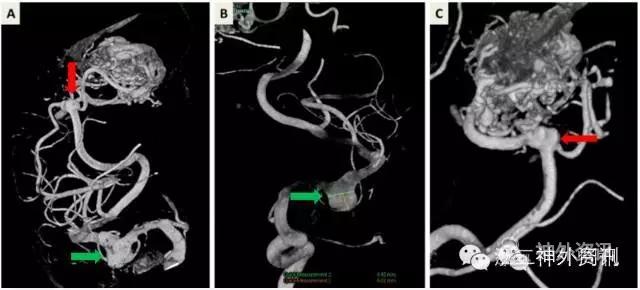

术后复查头颅CTA及DSA提示左侧M2中动脉动脉瘤和入畸形团分叉处动脉瘤夹闭完全,动静脉畸形团消失,未见残留,术区无明显出血(图6)。

图6. 术后复查头颅CTA及DSAA. 头颅CTA见术区无明显出血;B、C. DSA示动脉瘤完全夹闭(红绿箭头所示);D. DSA见动静脉畸形切除,未见明显残留。